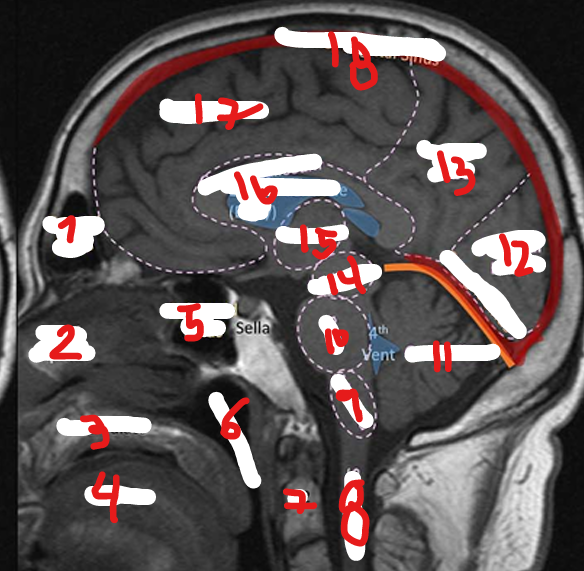

FRONTAL SINUS

1

<p>1</p>

39

New cards

NASAL SEPTUM

2

<p>2</p>

40

HARD PALATE

3

<p>3</p>

41

TONGUE

4

<p>4</p>

42

SPHENOID SINUS

5

<p>5</p>

43

NASOPHARNYX

6

<p>6</p>

44

FRONTAL LOBE

17

<p>17</p>

45

C2

7

<p>7</p>

46

SPINAL CHORD

8

<p>8</p>

47

MEDULLA

9

<p>9</p>

48

PONS

10

<p>10</p>

49

CEREBELLUM

11

<p>11</p>

50

OCCIPITAL LOBE

12

<p>12</p>

51

PARIETAL LOBE

13

<p>13</p>

52

MIDBRAIN

14

<p>14</p>

53

THALAMUS

15

<p>15</p>

54

CORPUS CALLOSUM

16

<p>16</p>

55

SUPERIOR SAGITAL SINUS

18

<p>18</p>